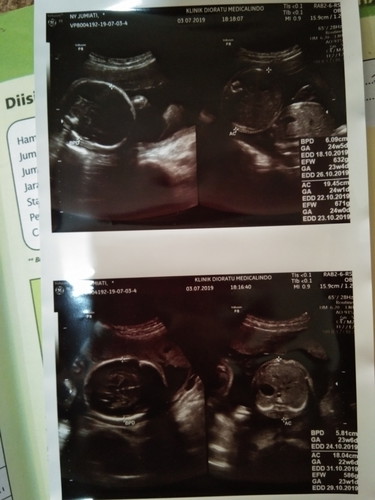

Ini maksudnya gimna yaa bun ?soalnya dokternya jelasin ga ngrti sya,,bilang doketrnya bayinya 2" sungsang bukan sungang kepala keats tapi kesamping bun? bagi tipis dong bun gimna caranya biar bisa normal 2"nya ?

Kembar ya bun? Uk berapa?